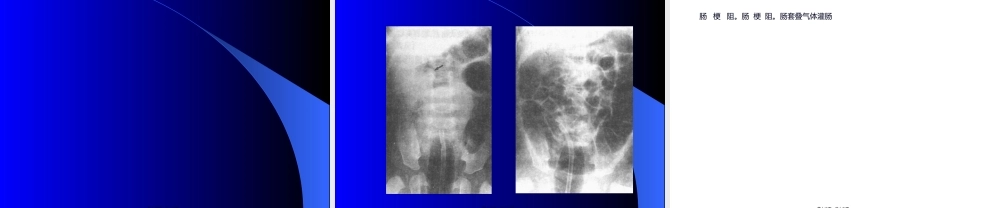

第一页,共十六页。第二页,共十六页。3、血运性肠梗阻〔二〕按肠壁有无血供障碍分1、单纯性肠梗阻2、绞窄性肠梗阻〔三〕按梗阻部位分〔四〕按梗阻程度分〔五〕按进展的快慢分二、病理〔一〕局部病变第三页,共十六页。1、肠蠕动增强2、肠膨胀3、肠壁血供障碍〔二〕全身病变1、体液丧失2、感染3、休克4、呼吸循环功能障碍第四页,共十六页。第五页,共十六页。4、停止自肛门排便排气〔二〕体征1、全身情况2、腹部体征:〔1〕视:〔2〕触:〔3〕叩:〔4〕听:3、直肠指检:第六页,共十六页。〔三〕实验室检查1、血:2、尿:3、呕吐物和大便〔四〕X线检查第七页,共十六页。第八页,共十六页。第九页,共十六页。第十页,共十六页。第十一页,共十六页。第十二页,共十六页。〔一〕根底疗法1、纠正水电解质紊乱和酸碱失衡2、胃肠减压3、防治感染〔二〕解除梗阻1、非手术治疗2、手术治疗第十三页,共十六页。第十四页,共十六页。第十五页,共十六页。内容总结肠梗阻。肠梗阻。肠套叠气体灌肠第十六页,共十六页。